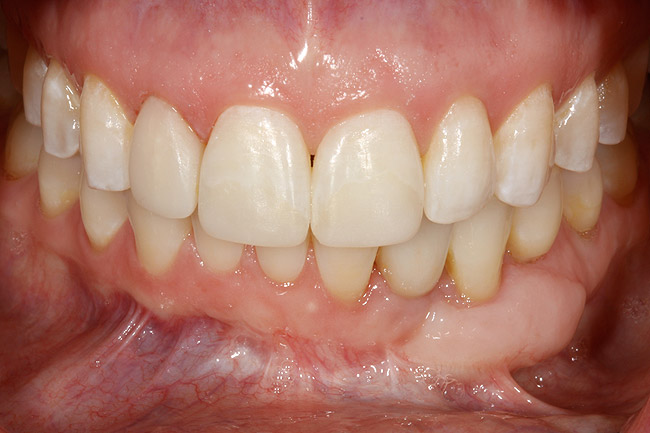

A 28-year-old Caucasian female presented to the periodontist with a complaint of a mobile implant in the site of tooth No. 22 (Figure 2 and Figure 3). The patient had a congenitally missing tooth No. 23. No. 22 had erupted into site No. 23, leaving a vacancy at site No. 22, and was the reason for the original implant at site No. 22.

Figure 2  A preoperative retracted anterior view of the failing implant in the site of tooth No. 22.

Figure 2